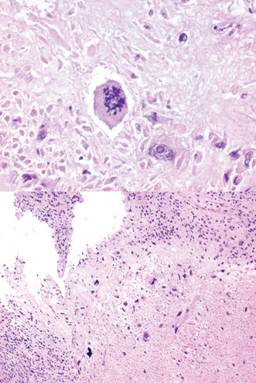

Figura 4: Microfotografía tumoral teñida con hematoxilina y eosina (H y E ), que demuestra atipia nuclear grado III, necrosis y múltiples mitosis atípicas.

El leiomiosarcoma de vagina representa el 0.62% de las neoplasias malignas del tracto reproductor femenino.3 Morfológicamente, se mencionan los tipos mixoide, epitelioide y convencional. Se caracteriza, sobre todo, por atipia celular, con más de 5-10 mitosis por campo, áreas de necrosis y un diámetro mayor de tres centímetros, lo cual también es factor pronóstico para recidiva.5 Suele diseminarse por invasión local y hematógena, teniendo como predominio metastásico el pulmón.